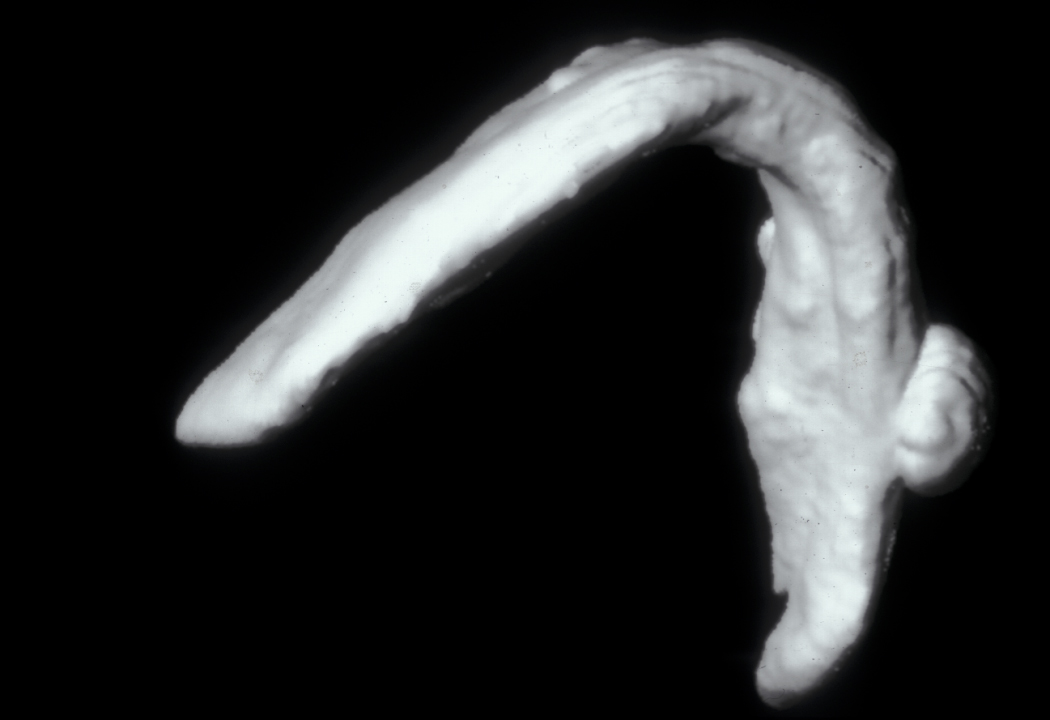

This condition has a number of different names and it occurs in approximately 3 % of routine tooth extractions, and up to 20 % of surgical tooth extractions. Figure 1 shows a dry socket, Figure 2 shows the radiograph of a severe case of dry socket.

Figure 1: Dry socket, a painful osteitis (bone inflammation) of the tooth socket.